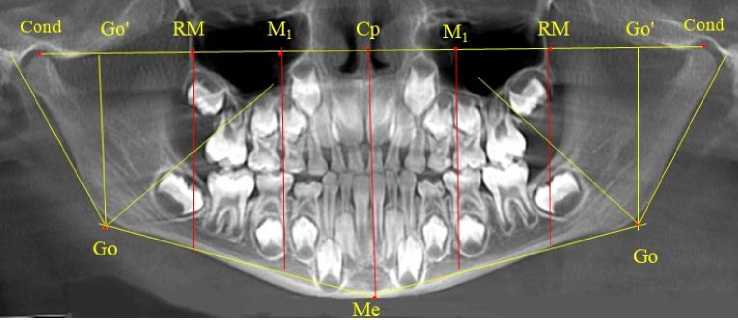

На ортопантомограммах устанавливались точки и линии, позволяющие оценить размеры зубоальвеолярных дуг и оптимальное положение дистально расположенных в окклюзии зубов. С этой целью на верхнюю точку суставной головки, с обеих сторон, устанавливали точки кон-дилион ( Сond ), которые соединяли суставной горизонталью. От середины суставной горизонтали проводили срединную вертикаль, которая, как правило, соединяла центральную (срединную) точку ( Ср ) с подбородочной точкой Ме .

Конструируемая точка гонион ( Go ) определялась традиционно при пересечении касательной линии к ветви челюсти с линией, соединяющей точку Go с нижней подбородочной точкой ментос ( Ме ), расположенной в нижней части подбородка по средней линии. От угловой точки Go строили перпендикуляр к горизонтальной суставной линии. На месте пересечения линий устанавливали точку Go ´. Предложенное построение обусловлено тем, что на ортопантомограмме, в отличие от телерентгенограммы, величина нижнечелюстного угла может быть искажена.

Расстояние между точками Go ´ и центральной точкой ( Central point ) Ср делили на коэффициент 1,5. Полученную расчетную величину откладывали от центральной точки на суставную горизонталь с обозначением точки (RM), от которой опускали перпендикуляр, который располагался в ретромолярной зоне и, как правило, проходил вблизи дистальных поверхностей задних зубов, ограничивающих зубоальвеолярные дуги. Кроме того, половина расстояния Ср-RM определяло положение молярной вертикали и точку на суставной горизонтали обозначали как М 1 (рис. 1).

Рис. 1. Анализ ортопантомограммы ребенка в периоде сменного прикуса при определении положения дистально расположенных зубов

Оптимальное положение нижних дистальных зубов определялось их расположением впереди стресс-оси, соответствующей биссектрисе гониально-ментального угла ( Go'-Go-Ме ).

Линия эстетического центра проходила от середины межсуставной горизонтали ( Cond-Cond ) и перпендикулярно к ней. Указанный ориентир проходил между медиальными резцами обеих челюстей до нижнего края подбородка (точка Ме).

Отношение отрезка суставной горизонтали от центральной точки (Ср) до проекции гонио-нальной точки (Go´) к коэффициенту 1,5 определяло расположение отправного точечного ориентира (RM) для построения ретромолярной вертикали перпендикулярно к суставной горизонтали. Особенностью исследуемого возрастного периода было то, что зачаток первого верхнего постоянного моляра при оптимальном окклюзионном соотношении располагался впереди ретромолярной вертикали. Данное обстоятельство свидетельствовало о благоприятном расположении зачатка, что в последующем обеспечивало его прорезывание по мере формирования корней. Кроме того, указанный размер (Ср-RM) определял зубоальвеолярный размер верхней челюсти (правой и левой). Молярная вертикаль, исходящая из молярной токи (М1), проходила через дистальные поверхности первых молочных моляров обеих челюстей (рис. 3).

Рис. 3. Анализ ортопантомограммы ребенка 4 лет в периоде прикуса молочных зубов

Зачатки первых постоянных моляров нижней челюсти располагались кпереди по отношению к биссектрисе угла Go´-Go-Ме , что так же, как и на верхней челюсти, оказывало благоприятное влияние на формирование и прорезывание нижнего первого моляра. Антимеры обеих челюстей располагались симметрично относительно диагностических линий.